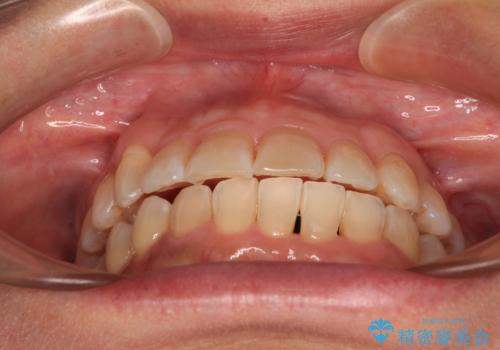

骨格のずれをカムフラージュ クロスバイトのワイヤー矯正

- 骨格的な咬み合わせのズレ、前歯のデコボコとクロスバイトを気にして来院された患者様です。

下顎の正中を歯1本分ずらした位置とすることで、外見上の骨格的なずれをカバーするように計画しました。

クロスバイトを改善したことで、前歯の負担が軽減し、安定して噛めるようになりました。